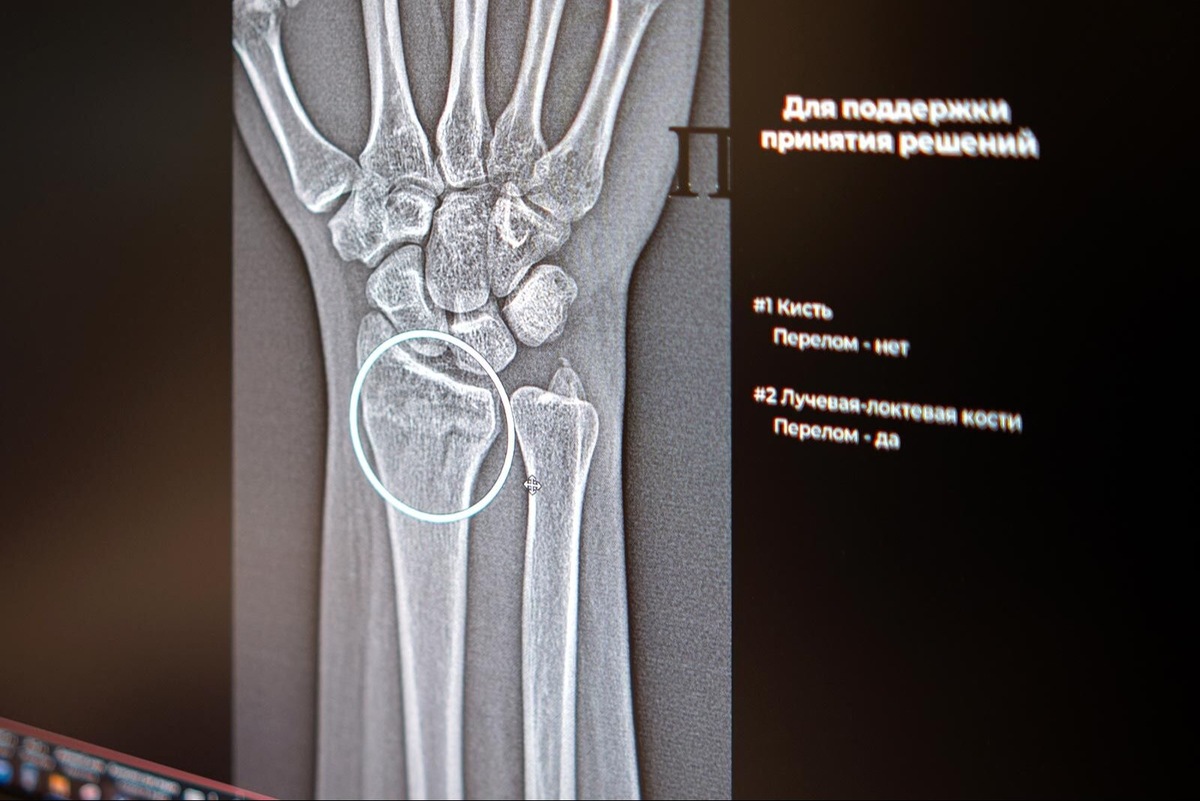

Цифровые ассистенты анализируют рентгеновские снимки и автоматически отмечают повреждённые участки, даже если на изображении видны признаки сразу нескольких переломов. Как отметила заместитель Мэра Москвы по вопросам социального развития Анастасия Ракова: «Цифровые решения уже более пяти лет помогают столичным рентгенологам — прежде всего, в анализе медицинских снимков. Недавно мы запустили два новых ИИ-сервиса, которые помогают обнаруживать на рентгеновских изображениях травмы костей голеностопного и лучезапястного суставов — одних из самых функциональных и при этом уязвимых».

Алгоритмы не только отличают норму от патологии, но и выполняют точные измерения границ и размеров повреждений. Особенно ценно, что искусственный интеллект способен заметить даже минимальные трещины, которые могут ускользнуть от человеческого глаза.

«Травмы предплечья, кисти и голени встречаются достаточно часто. Диагностика перелома включает осмотр травматолога с последующим выполнением рентгенографии. Специалисты используют ИИ-алгоритм как инструмент, способный повысить точность и скорость анализа лучевого изображения, что критически важно для постановки диагноза», — пояснил главный внештатный специалист по лучевой и инструментальной диагностике Москвы Юрий Васильев.